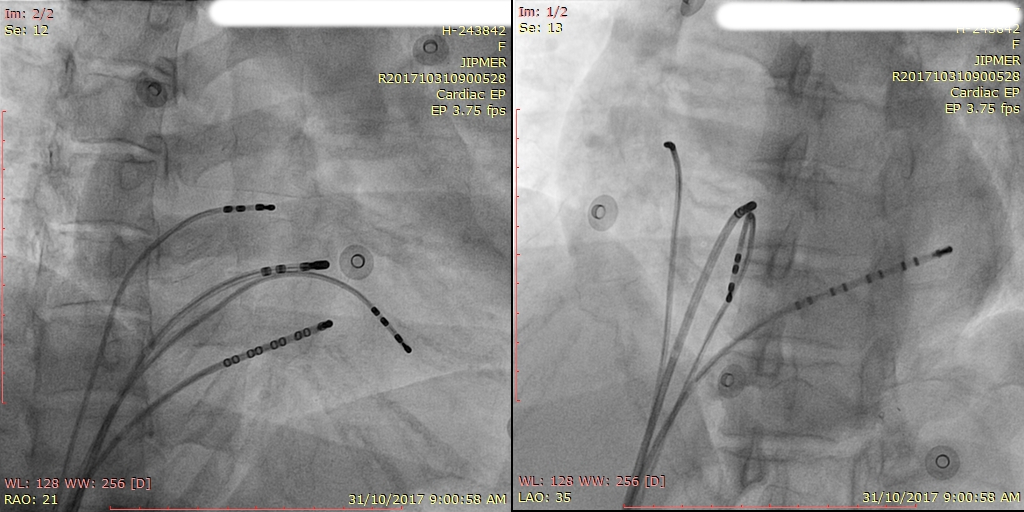

Imaging

Fluoro

• Digital flat panel detector

• Bi plane preferable if possible

• Integrated data display system

What frame rate is suitable for EP studies ?

• A. 3.75 fps

• B. 7.5 fps

• C. 15 fps

• D. 30 fps